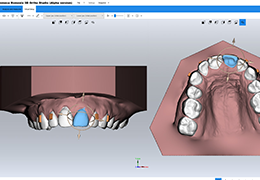

Everyone – including surgeons, patients and their loved ones – benefits from being better informed by the wealth of information buried within CT and MRI scans. Pro Surgical 3D gives surgeons more information to develop optimal treatment plans for patients. It also helps patients and their support group better understand their medical condition and proposed treatment options.

Better understanding of a condition, disease or diagnosis

Ability to clearly see the condition or disease

Better understanding of treatment options

High-quality and fast 3D reconstruction and 3D rendering

Performs 3D reconstruction and volume rendering.